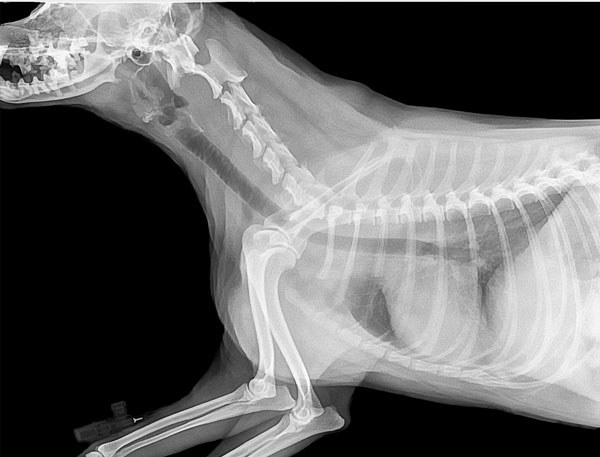

La clinique MidiVet dispose d’un appareil de radiographie numérique. Devenue la référence en radiographie, l’imagerie numérique permet d’obtenir des images de qualité bien supérieure à celle des anciennes images argentiques. De plus la numérisation permet un archivage et une transmission facile des résultats, par mail par exemple. Enfin, à l’inverse des anciennes techniques de développement argentique, le développement numérique n’utilise pas de produits chimiques néfastes pour l’environnement.